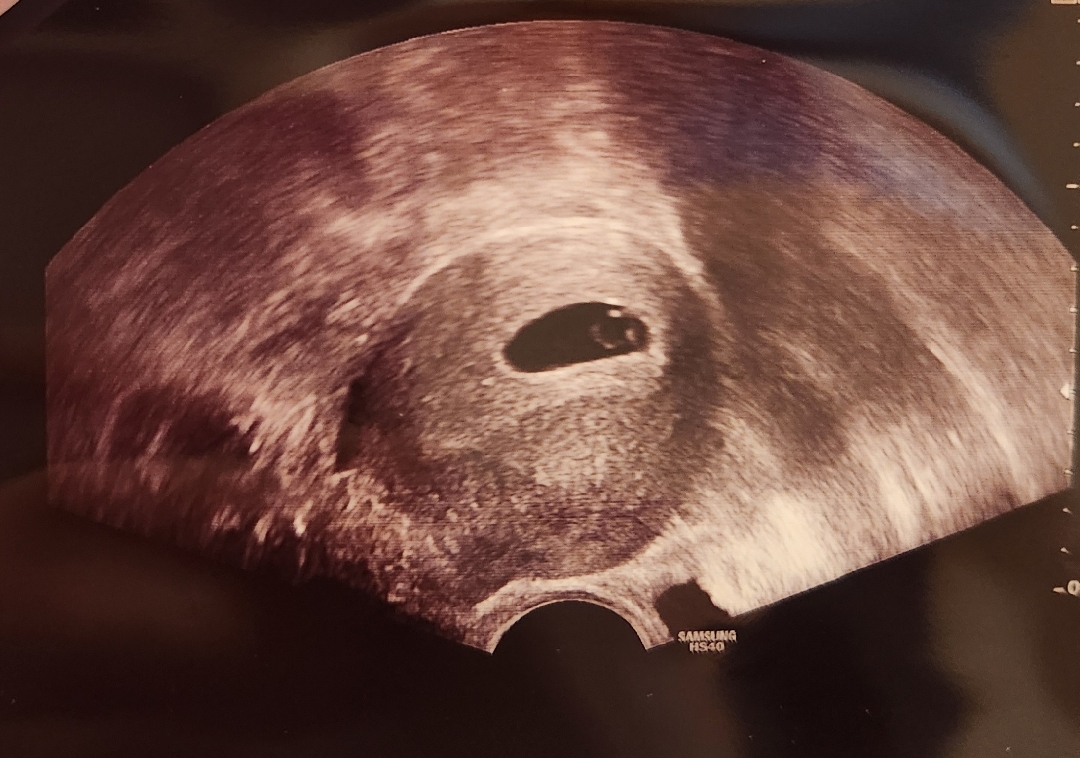

5주6일 심장소리 들었어요 ㅎㅎ

아직 6주 전이라 들을 수 있으려나 했는데 아주 작게 들렸어요! bpm은 103이라고 하네용 4주에 아주 작은 아기집 보고 그새 이렇게 큰 게 신기하네요😃